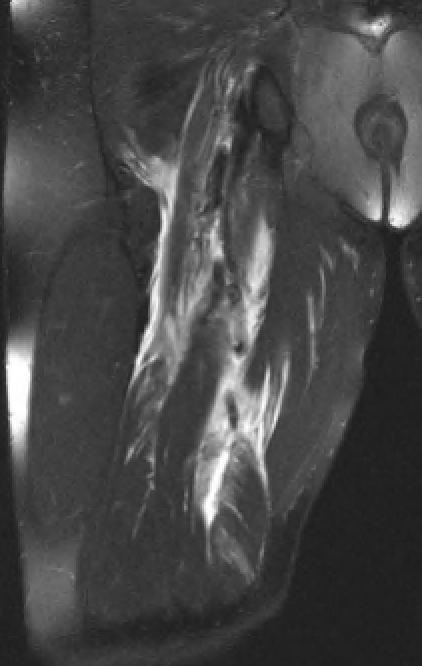

Proximal hamstring tear on right (red circle), normal insertion on tuberosity on left (blue circle)

Proximal hamstring avulsion on right - red circle is retracted hamstring tendon, blue circle is normal insertion on left

Proximal hamstring tear on right (red circle), normal insertion on left (blue circle)

Proximal hamstring avulsion, with tendon floating in hematoma / seroma